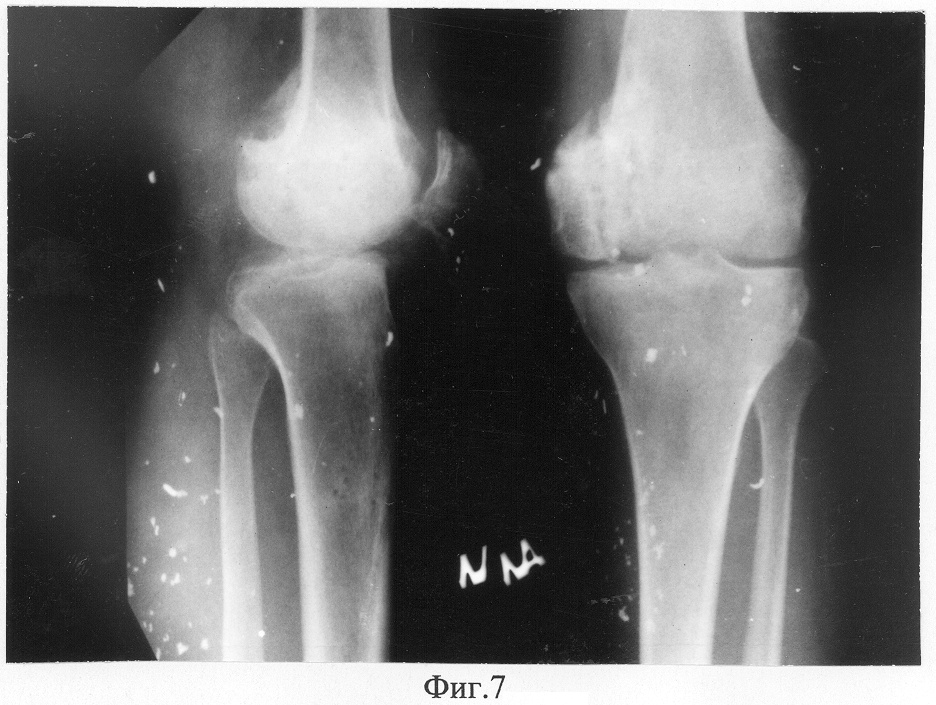

Фиг.7 – рентгенограммы коленного сустава пациента в прямой и боковой проекциях с максимальным разгибанием через 1 год после снятия аппарата;

Достигнуто сращение мыщелка бедренной кости с восстановлением артикулирующих поверхностей коленного сустава и биомеханической оси конечности (Фиг.7, 8). Длина ног одинаковая. Ходит не хромая, боли отсутствуют, устойчивость голени полная. Объем движений в коленном суставе перераспределен в функционально выгодный диапазон (100°-180°).